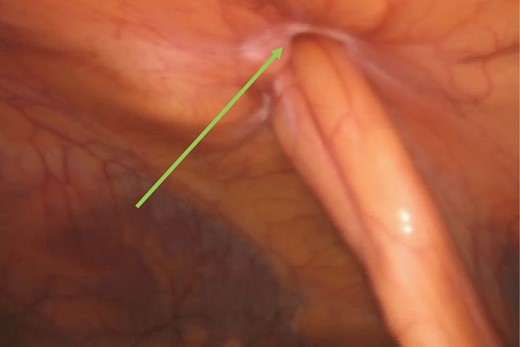

A computerized tomography (CT) scan demonstrated a chronic ventral hernia (Fig. 1) containing fat anterior to the left lobe of the liver which had marginally increased in size from a previous study done a year earlier. Through judicious use of analgesia, the hernia was successfully reduced. Two weeks later, the patient underwent a laparoscopic transabdominal pre-peritoneal (TAPP) mesh repair (Fig. 2). Laparoscopic visualization revealed, along with viable incarcerated omentum (Fig. 3), a falciform ligament hernia extending into the abdominal wall in the epigastrium.

Incarcerated omentum (green arrow) within the falciform ligament (black arrow).